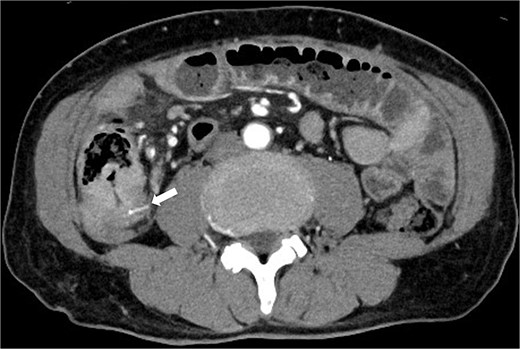

A 63-year-old man presented with recurrent right lower abdominal pain. Blood tests showed mildly elevated C-reactive protein (CRP), dehydration, and a high alpha-fetoprotein (AFP) of 2659 ng/ml. Computed tomography (CT) revealed a high-density area in the small intestine of the right lower abdomen, which was suspected to be a foreign body, with circumferential wall thickening in the same area (Fig. 1). The intestinal tract on the oral side of the area was dilated, and small intestinal obstruction due to chronic inflammation caused by the foreign body was suspected.

Preoperative CT revealed a high density area in the small intestine of the right lower abdomen, which was suspected to be a foreign body, and a circumferential wall thickening in the same area. The intestinal tract on the oral side of the area was dilated, and small intestinal obstruction due to chronic inflammation caused by the foreign body was suspected.